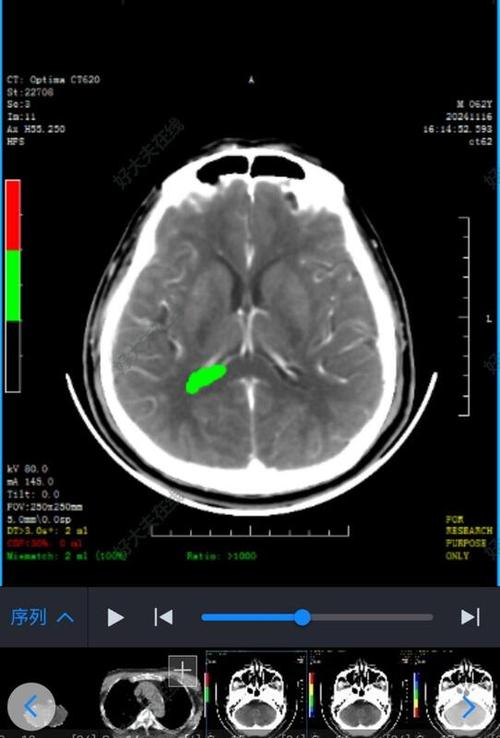

- 腔隙性脑梗:

- CT表现:这是脑梗的一种特殊类型,由深部小血管堵塞引起,表现为很小的(通常小于15毫米)、圆形或卵圆形的低密度灶,很多患者没有症状,是偶然发现的。